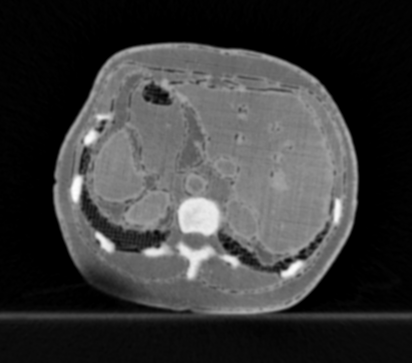

3.1.3 Example 2: data driven reconstruction methods in lung CT screening

There is sufficient evidence that screening for certain tumours using CT images may improve prognosis of cancer survivability (citep \@BBN(Boiselle, 2013)). As mentioned above, in order to gain better image quality with less X-ray dose, many enhanced regularization techniques with integrated machine learning steps have been suggested for CT reconstruction, and in a full reference setting they are commonly evaluated by applying PSNR and SSIM, see e.g. (citep \@BBN(Adler and Öktem, 2018; Hendriksen, Pelt, and Batenburg, 2020; Unal, Ertas, and Yildirim, 2021)). As CT images are generally taken to perform a clinical task, they are not the final step of a medical process but often the initial one. Therefore the definition of what makes a good image heavily depends on the task in hand, and for prognosis related cancer the identification of tumours is of upmost importance.

In on-going research on photon counting detector types and screening procedures for lung cancer (EPSCR grant: EP/W004445/1) an experiment was conducted testing enhanced reconstruction algorithms. Simulations using less than 10% of a clinical X-ray dose were performed to investigate if data-driven methods could sufficiently enhance the images to clearly see the tumours in the lungs while providing very low amount of dosage to the patients. The corresponding data was a CT-dose simulation, using images from the open LIDC-IDRI dataset (citep \@BBN(Armato et al., 2011)) as references, as well as simulated and reconstructed images with in-house software. Figure 3 shows the results of the experiment. We show the reference image used as basis for the simulation, together with five different reconstruction algorithms. The first is an iterative solver, a gradient descend algorithm with TV minimization (citep \@BBN(Sidky et al., 2012)) and (c)-(f) correspond to machine learning methods: FBPConvnet is a denoising algorithm that cleans the bad image (citep \@BBN(Jin et al., 2017)), LPD is an iterative unrolled method that combines traditional solvers with machine learning (citep \@BBN(Adler and Öktem, 2018)), Noise2Inverse is a self-supervised learning method (i.e. does not require ground truth data) (citep \@BBN(Hendriksen et al., 2020)) and ItNet is another iterative unrolled method, the best performing winner of the AAPM DL-Sparse-View CT challenge (citep \@BBN(Genzel, Macdonald, and März, 2021)). ItNet is also judged here as the best result according to PSNR, SSIM and LPIPS.

Refer to caption

(a) Reference

(b) (27.6, 0.70, 0.37)

(c) (31.9, 0.73, 0.29)

(d) (32.5, 0.84, 0.19)

(e) (32.5,0.77, 0.20)

(f) (33.0, 0.89, 0.12)

Figure 3: Reference image (a) and outputs of different reconstruction methods (b)-(f) applied to dose simulated data. PSNR/SSIM/LPIPS are unable to identify the best reconstruction (c), where also the tumour is visualized well.

FR-IQA mismatches

This experiment was performed to evaluate the quality of different kinds of CT reconstruction, and especially the lung tumour detection capabilities thereof. The best result according to the chosen IQA measures is given by ItNet in Figure 3(f), which performs visually poorly. Not only the tumour (zoomed in white circle) is significantly less visible in the reconstruction, but ItNet also produces structures in the lung that are different than the ones in the reference image; it blurs and lengthens much of the soft tissue present in the lungs and it also created structure from noise in some places. Moreover, the image is overly smooth. Comparing the other reconstruction algorithms, it seems that FBPConvnet Figure 3(c) is the one performing best at preserving the shape of the lung nodule, even when the resulting image contains enhanced pixel-level noise.

We can see here that the qualitative findings strongly contradict the numbers provided by the selected measures. The reconstruction of ItNet, Figure 3(f), is outperforming the other reconstructions in regards of the measures, and the qualitative winner FBPConvnet, Figure 3(c), is judged as second worst by the same measures. This experiment suggests that the discussed measures are not a good choice for that kind of CT reconstruction applications and are yielding misleading results.

While pixel-independent random noise may be a worse effect in a natural image than a slightly oversmooth reconstruction, this is not true in CT images, where small structures may disappear if smoothing is promoted against edge preservation. In iterative reconstruction algorithms such choices are explicitly made by choosing the prior appropriately, in data-driven models the researcher has limited control on the type of implicit priors the algorithm learns from the data, i.e. model builders do not know what the algorithms chooses to learn from the ground truth. In these cases appropriate evaluation would be even more important to ensure the described quality properties.